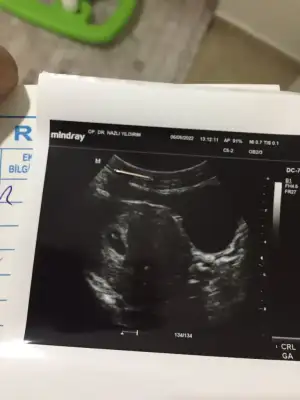

paşa mı sankiMerhaba 6+4 vajinal ultrason görüntüsüne yorum yaparmısınız çok merak ediyorummEki Görüntüle 3069814

Canım benim fotoğrafımı da yorumlar mısın 7 hafta karındanben kız olarak yorumladım ama bu de sen bak

Ben de merak ediyorum:) karından 6 haftalıkSelam Kızlarbir çok kişi gruplardan beni bilir. Yine yetiştim imdatlara

Geç oldu ama 7+1 buna da bakar mısınız

Evet karından bakildikarından mı bakıldı?